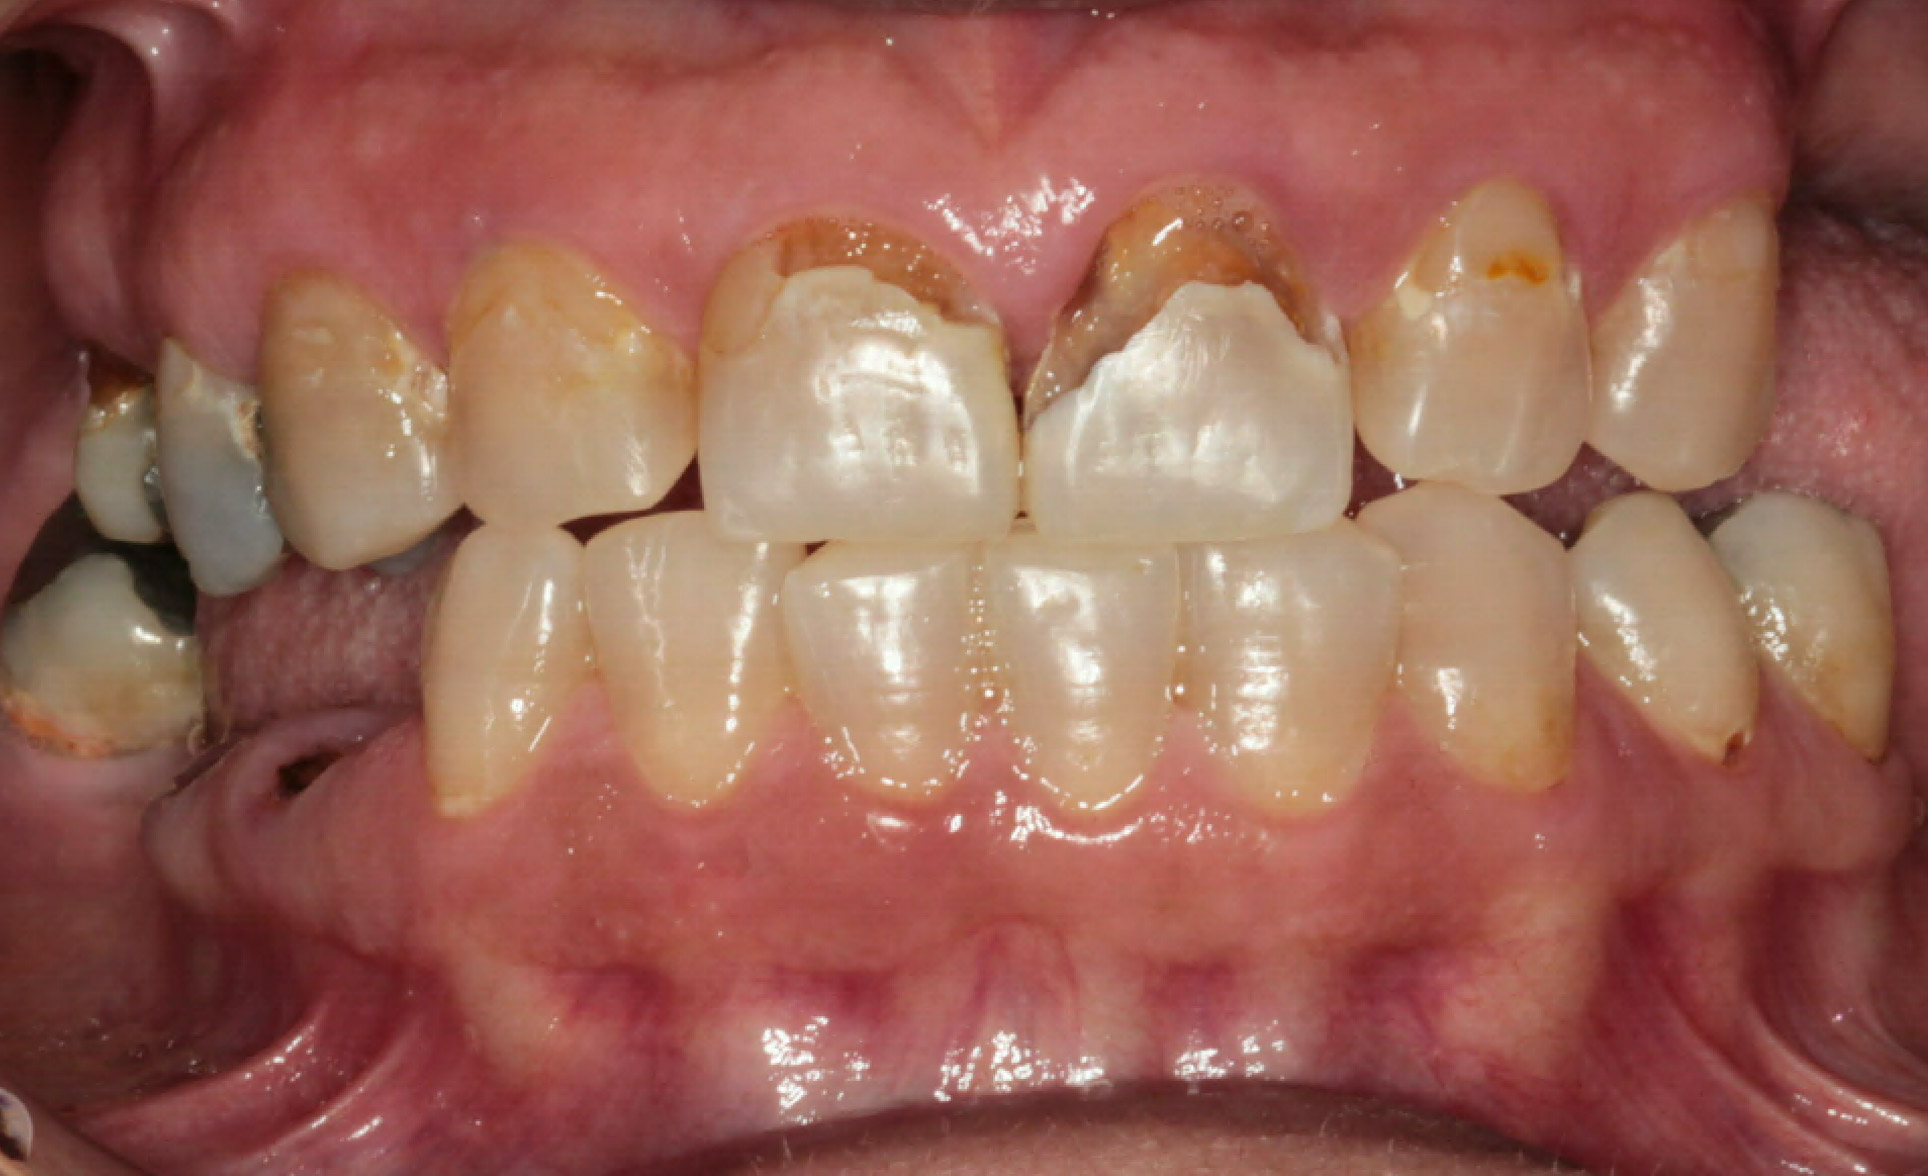

VII. INTRA ORAL PICTURES

Intra Oral Pictures (1)

(Treatment in progress)

Intra Oral Pictures (3)

Intra Oral Pictures (4)